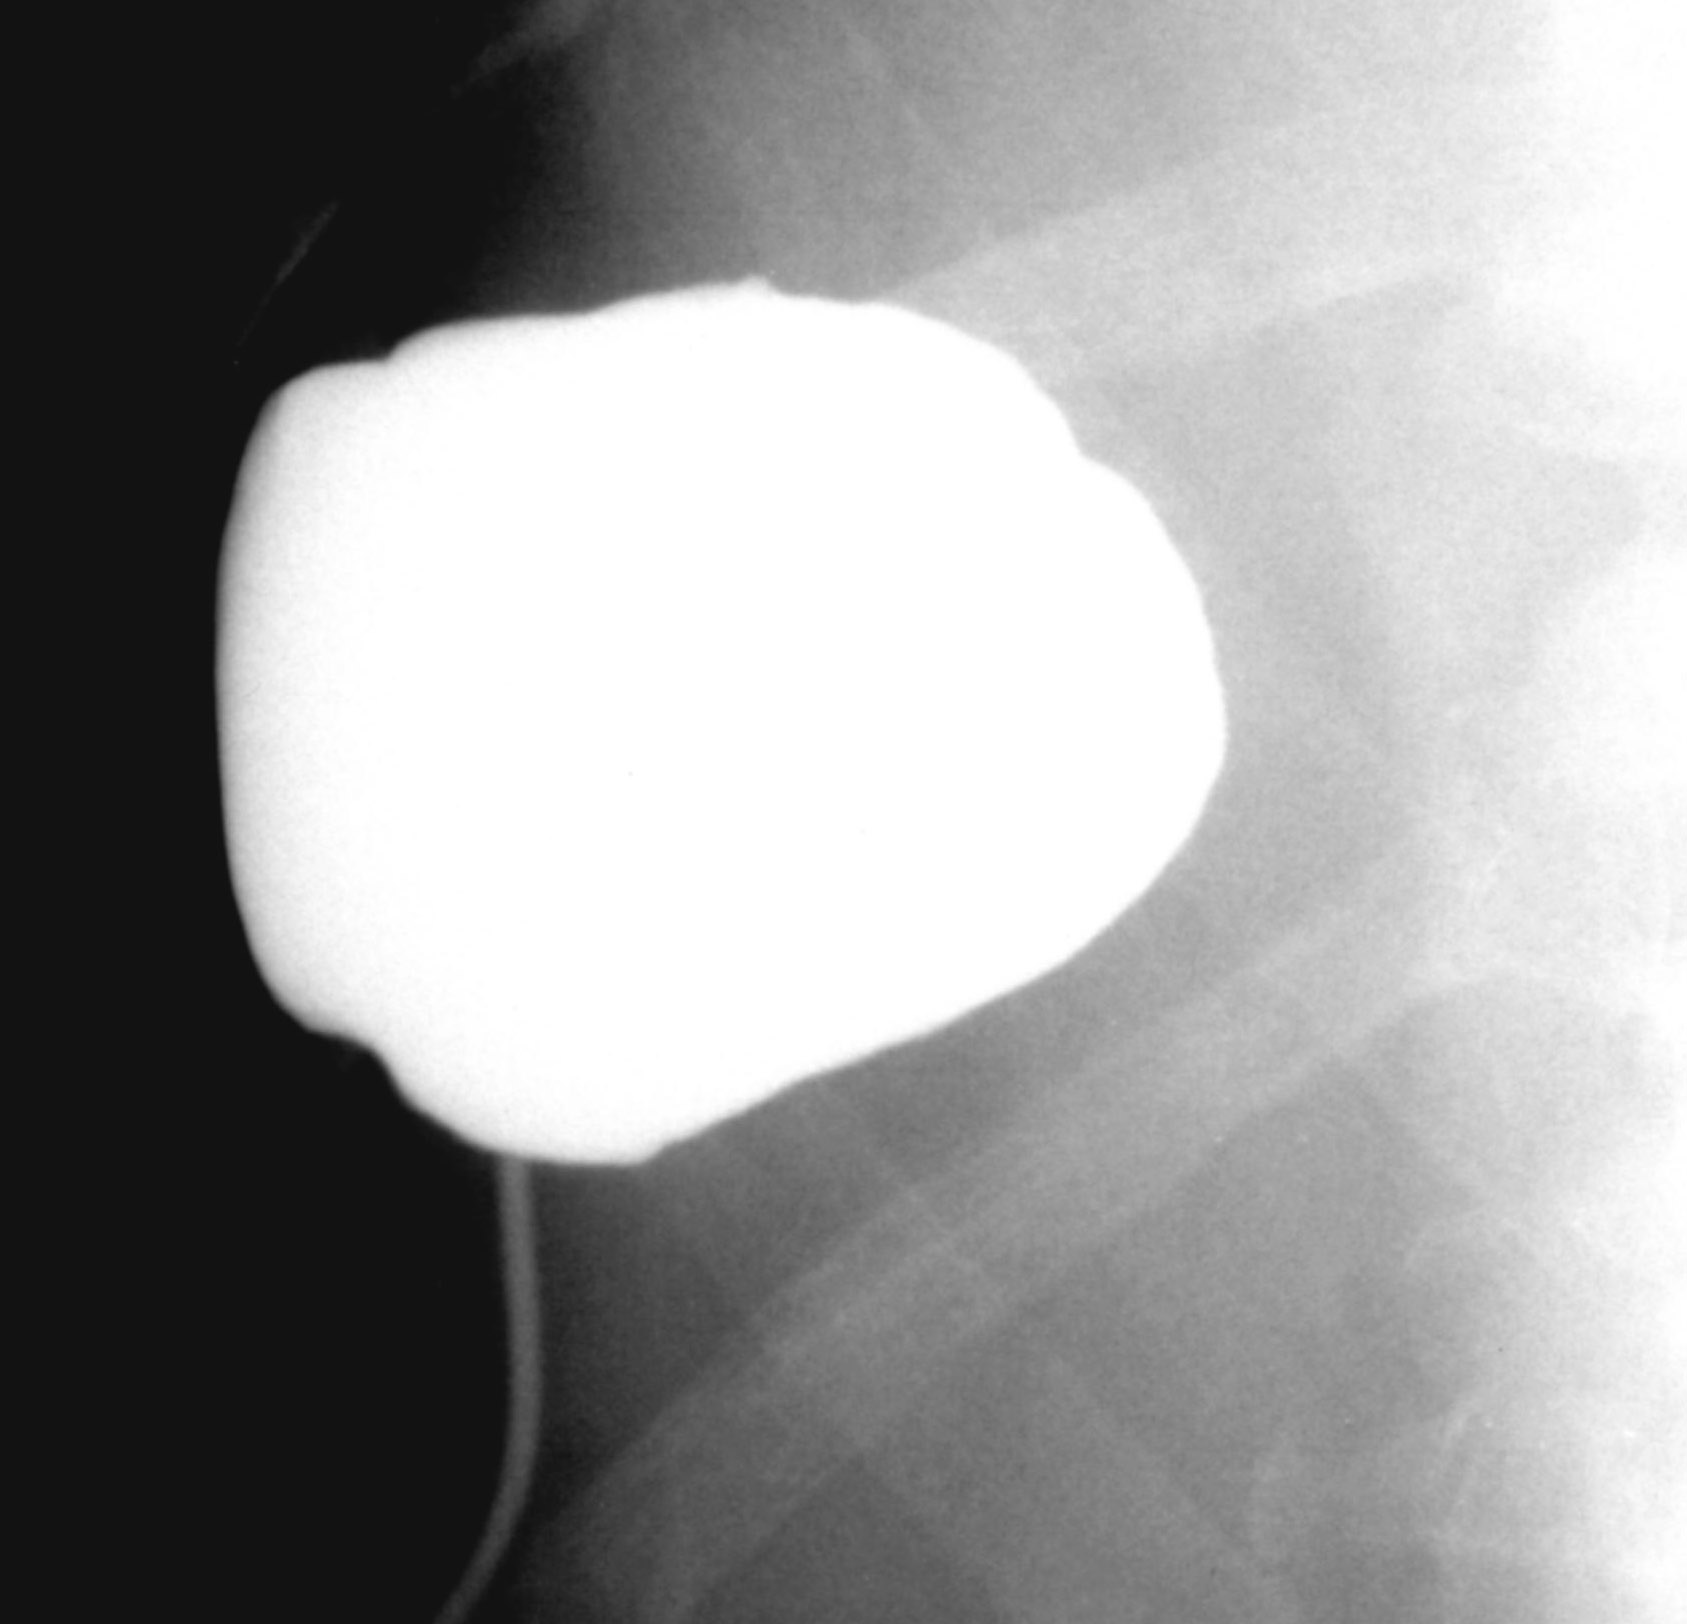

Usually in case of elderly patients and in case of certain types of acalculous cholecytitis US guided percutaneous drainage of the gall bladder proves to be a very effective technique. (Figure 25.)

Image

Figure 25. – Percutaneous cholecystostomy (85 years old, female patient in poor general condition. Percutaneous intervention due to acute cholecystitis.)

During the procedure one needs to carry out the puncture or the insertion of the drain from the parenchymal side of the cholecyst. Puncture on the free side of the cholecyst can lead to serious complications, intraabdominal bile leakage, bile peritonitis.